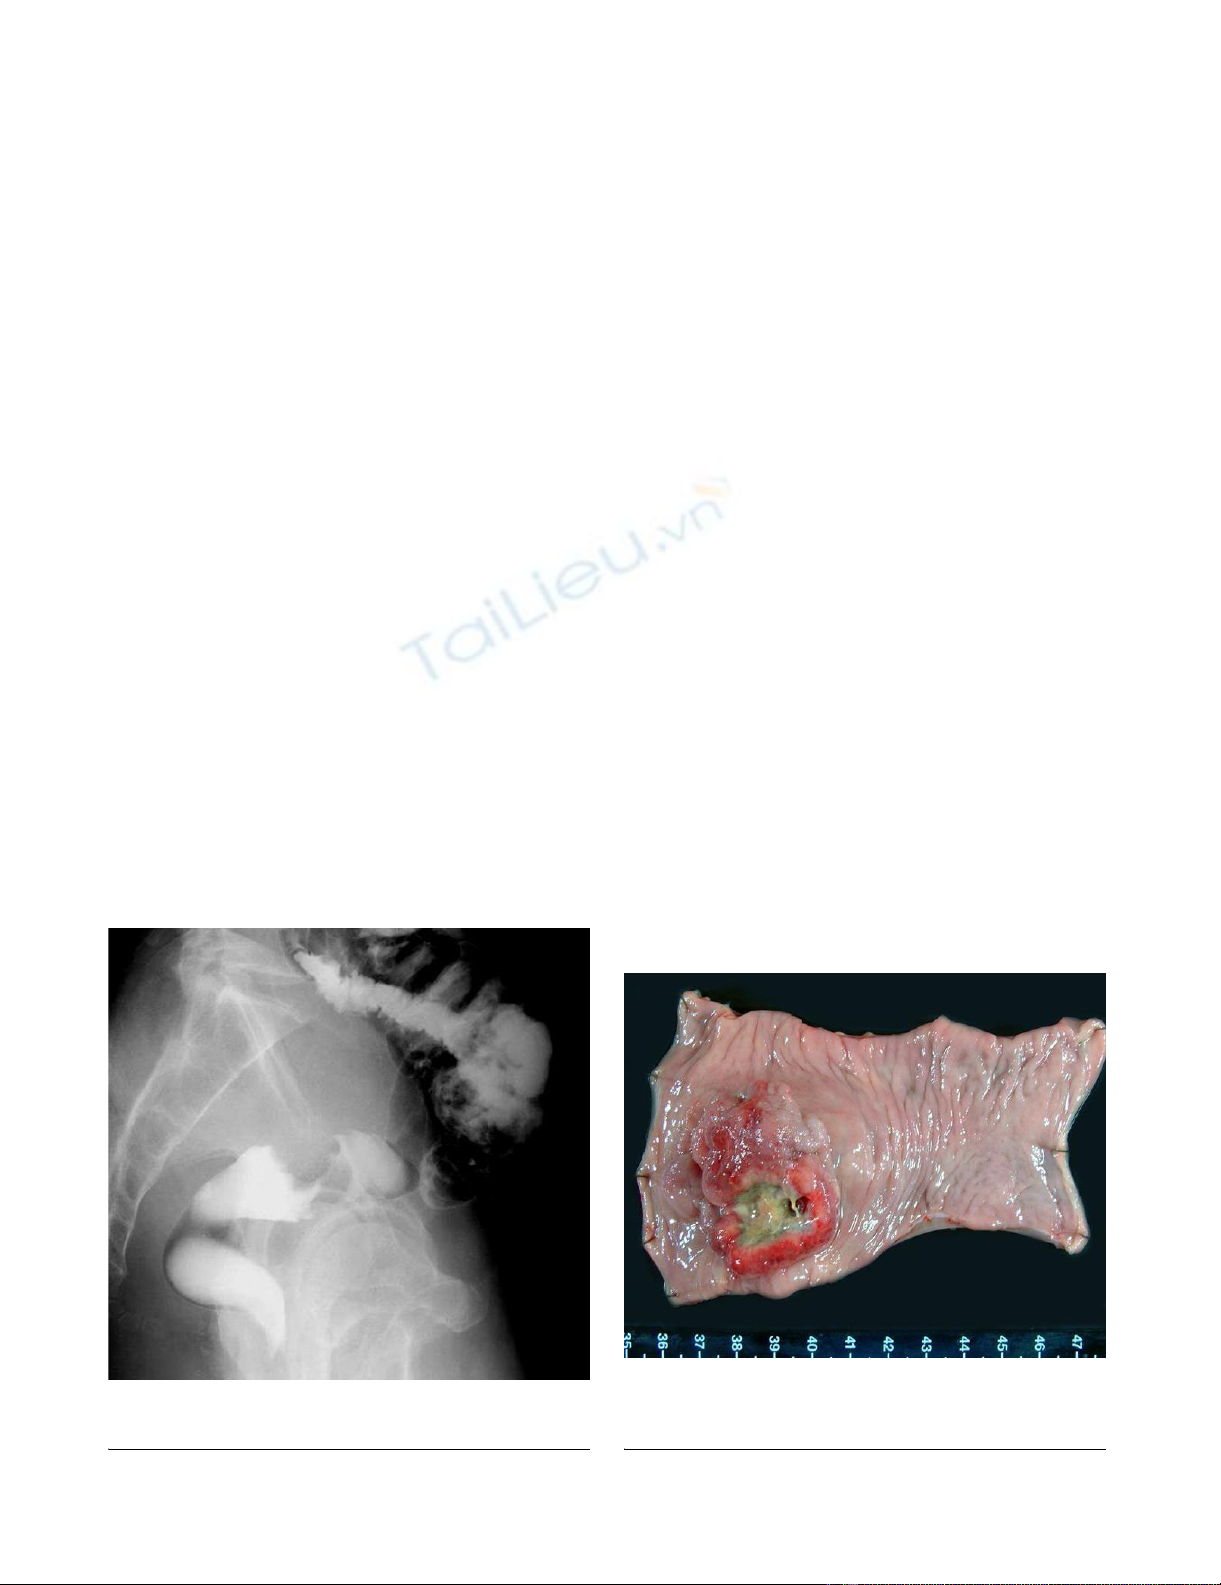

Resected specimenFigure 2

Resected specimen. An ulcerated hard tumor was present in

the rectum.

Barium enema revealed an ulcerative tumor in the rectumFigure 1

Barium enema revealed an ulcerative tumor in the rectum.

An ulcerated hard tumor was present in the rectum (Figure

2). Histopathological examination revealed that the

tumor consisted of large abnormal cells without gland for-

mation and mucin production (Figure 3a). Immunohisto-

chemical studies were positive for cytokeratin and

vimentin; however, they were negative for CD45 and PAS.

In addition, they were negative for both neuron-specific

enolase (NSE) and synaptophysin, and histologic staining

with alcian blue was also negative. Therefore, we diag-

nosed this case to be an undifferentiated carcinoma of the

rectum. A small component of well-differentiated adeno-

carcinoma was also seen on the surface of the tumor (Fig-

ure 3b). Thus, we thought that we diagnosed this tumor as

well-differentiated adenocarcinoma at biopsy. Advanced

lymphatic vessel and venous invasion were observed.